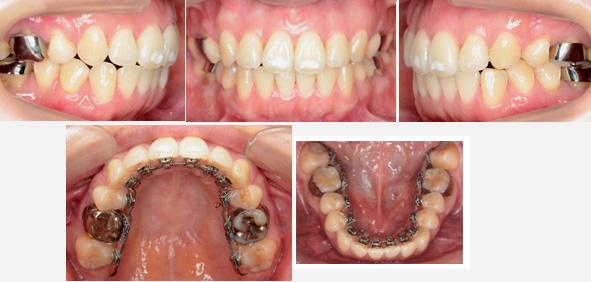

来院時の写真

気になっている点(主訴): 翼状捻転 出っ歯

上顎中切歯(一番前の歯)が逆はハの字になっています。これはまさに翼状捻転です。横から見ると前歯が対照的に捻転しながら前歯が外に飛び出した状態です。

治療中の写真

あともう少しで装置が外れます。患者さんは接客業を仕事にしています。

上顎中切歯が対照的に捻じれています。典型的な翼状捻転です。

抜歯部位 : 上顎両側第一小臼歯

治療に使用した装置 : リンガルブラケット

治療期間 : 24か月

翼状捻転を歯を抜かずに治すと、この患者様の場合は出っ歯(上顎前突)になってしまいます。このために上顎の小臼歯だけを抜歯して排列しました。患者様は接客業をされています。リンガルブラケットは周囲の人に気づかれる事はありません。